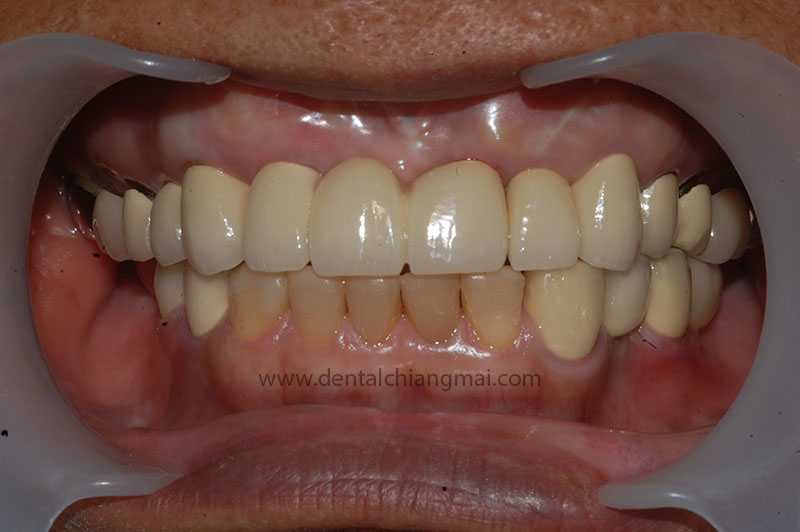

CASE 1 : 5 implants with 3 unit Bridges on upper front maxilla.

After: